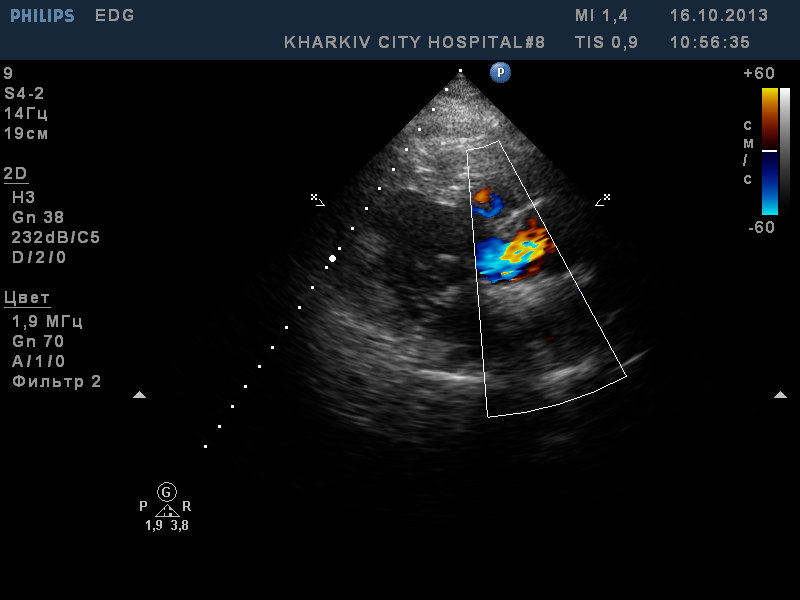

пациентка 49лет. ВПС- «единственный желудочек» со смещением аорты, легочным стенозом (Pgmax65мм рт.ст). Малая структурная аномалия — сеть Киари.